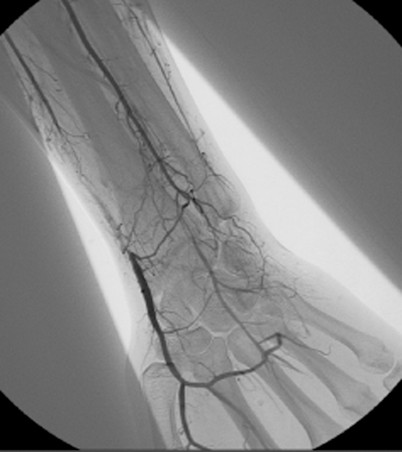

Deutsch Auch Morbus WiniwarterBuerger oder WiniwarterBuergerSyndrom Endangiitis obliterans Krankheit Medium hochladen Wikipedia Ist ein(e) Krankheit, designated intractable/rare diseases Unterklasse von arterial occlusive disease, predominantly mediumvessel vasculitis, secondary glomerular disease Benannt nach. Ischämie» die Differentialdiagnose eines Morbus WiniwarterBuerger erwogen Die selektive Angiographie vom zeigte die typischen «KorkenzieherKollateralen» am rechten Unterschenkel (Abb 1 x) Eine Ilomedintherapie war allerdings nicht erfolgreich, so dass am 1302 eine Grosszehenamputation rechts durchgeführt werden musste. Synonyme Morbus WiniwarterBuerger, VonWiniwarterBuergerKrankheit, Endarteriitis obliterans, Thrombangiitis obliterans Englisch endangitis obliterans, Buerger's disease Inhaltsverzeichnis.

Buerger related the cellular nature of arterial thrombosis, as had von Winiwarter, and described the absence of large vessel involvement It was Buerger who named the disorder “thromboangiitis obliterans”, and only briefly mentioned its relationship with smoking In 1924, Buerger reported that tobacco use was probably a predisposing factor 2. Morbus WiniwarterBuerger Stuttgart, Germany Georg Thieme;. Ischämie» die Differentialdiagnose eines Morbus WiniwarterBuerger erwogen Die selektive Angiographie vom zeigte die typischen «KorkenzieherKollateralen» am rechten Unterschenkel (Abb 1 x) Eine Ilomedintherapie war allerdings nicht erfolgreich, so dass am 1302 eine Grosszehenamputation rechts durchgeführt werden musste.